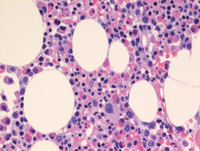

Figure 2: Lymphocytic variant of HES-Bone marrow biopsy H&E

Bone marrow is mildly hypocellular for age (40% cellularity) as evident on low power photomicrograph on the left. High power photomicrograph (right) shows increase in eosinophils and eosinophilic precursors, scattered throughout the marrow. Trilineage hematopoiesis is seen with adequate maturation. Bone marrow showed less than 4% blasts and no overt dysplasia was observed. Additionally, no increase in marrow fibrosis was observed on reticulin stain.